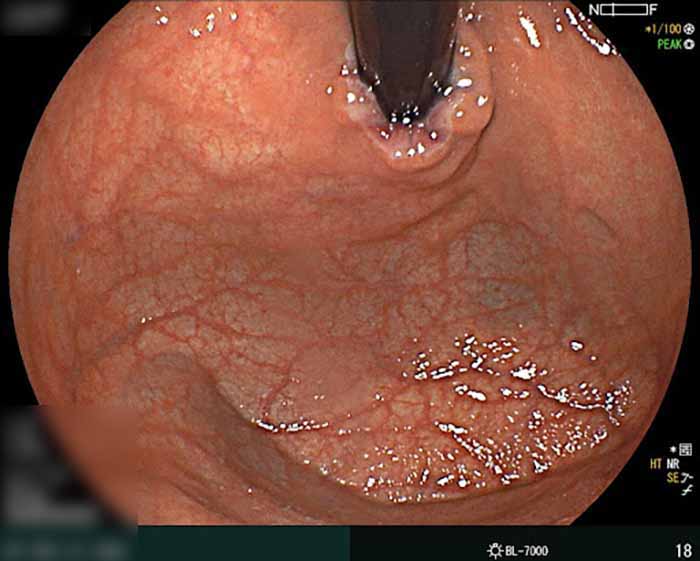

Nội soi dạ dày dương tính nghĩa là có phát hiện tổn thương hoặc bất thường trong dạ dày thực quản, thường gặp nhất là viêm, loét, trào ngược gây viêm, polyp hoặc nhiễm vi khuẩn HP trong dạ dày. Kết quả này cho thấy dạ dày không hoàn toàn khỏe mạnh và cần được bác sĩ điều trị hoặc theo dõi tùy mức độ.

- Viêm dạ dày: Niêm mạc bị đỏ, phù nề cho thấy dạ dày đang bị kích ứng hoặc viêm kéo dài, có thể gây đau âm ỉ, đầy hơi, khó tiêu.

Nội soi dạ dày dương tính chứng tỏ bị nhiễm HP trong dạ dày